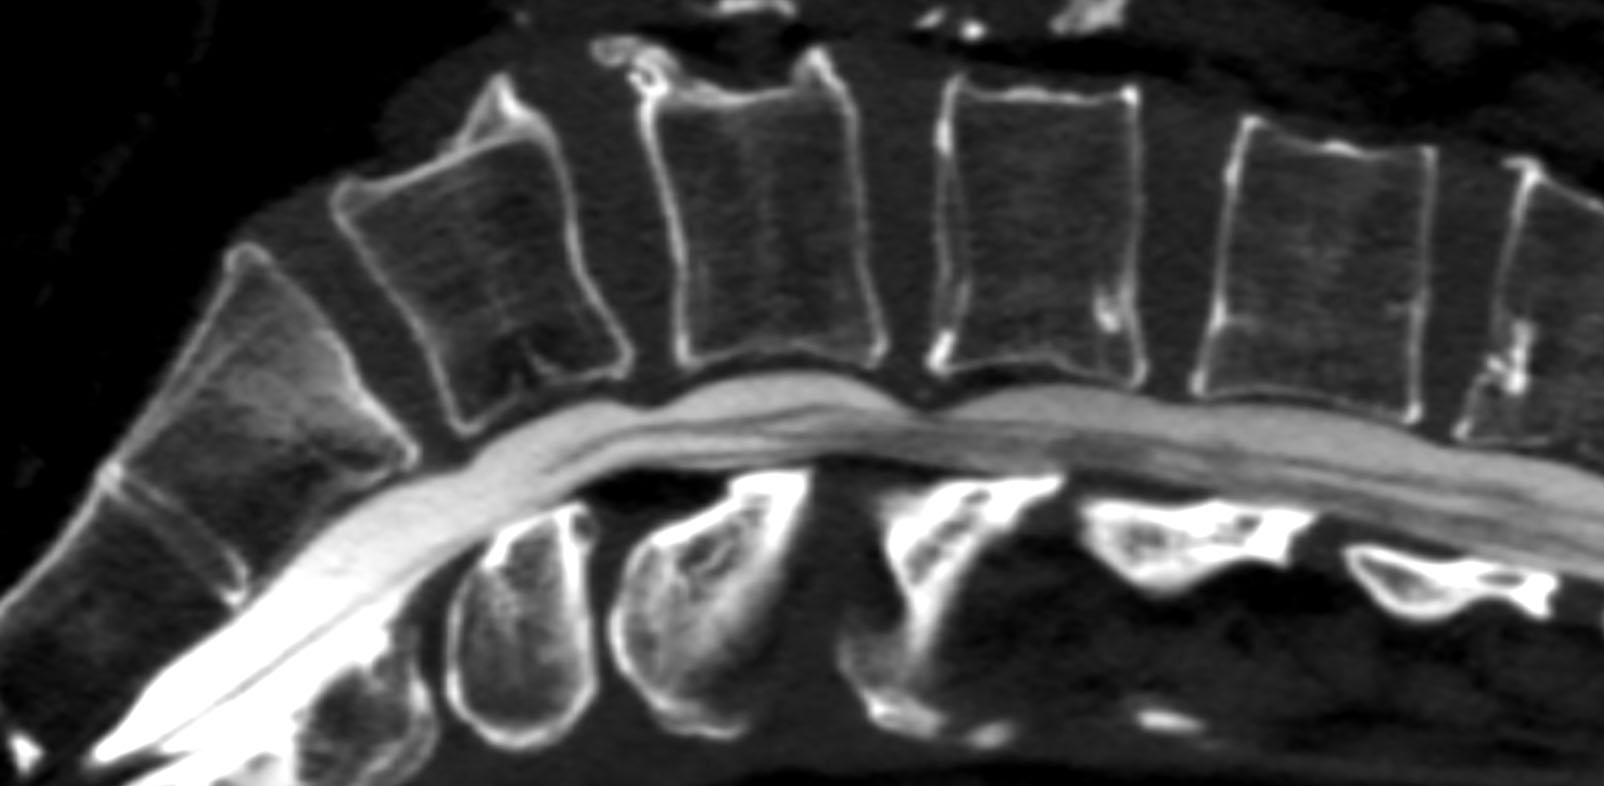

Prima dell'avvento della risonanza magnetica, lo studio tramite mielografia rappresentava l'unico metodo per poter visualizzare direttamente il canale spinale contenuto nello scheletro osseo della colonna vertebrale. Il concetto che sta alla base di questa procedura è l'introduzione, mediante puntura diretta, di un mezzo di contrasto specifico all'interno degli spazi subaracnoidei perimidollari o del sacco durale. In questo modo è possibile visualizzare questi spazi che sono normalmente riempiti di liquido e normalmente non direttamente visibili ai raggi-x. La metodica tradizionale con controlli radiografici e radioscopici viene ulteriormente migliorata dalla possibilità di effettuare una scansione TAC o TC dopo l'introduzione del farmaco: grazie alle apparecchiature attuali è cosi possibile effettuare studi ad altissima risoluzione sul sacco durale , il contenente e il contenuto, in particolare sulle radici nervose e le emergenze delle stesse.

L'esame può seguire iter differenti a seconda del tipo di studio o indicazione clinica. Il paziente può essere seduto lateralmente sul tavolo radiografico oppure disteso in posizione prona sul lettino TC. Il radiologo esegue un reperaggio con immagini ed inserisce un ago spinale nella parte centrale della colonna (può essere utilizzata o meno una piccola anestesia locale). Una volta raggiunto lo spazio subaracnoideo viene iniettato il liquido di contrasto, in seguito vengono effettuate le acquisizioni per immagini.